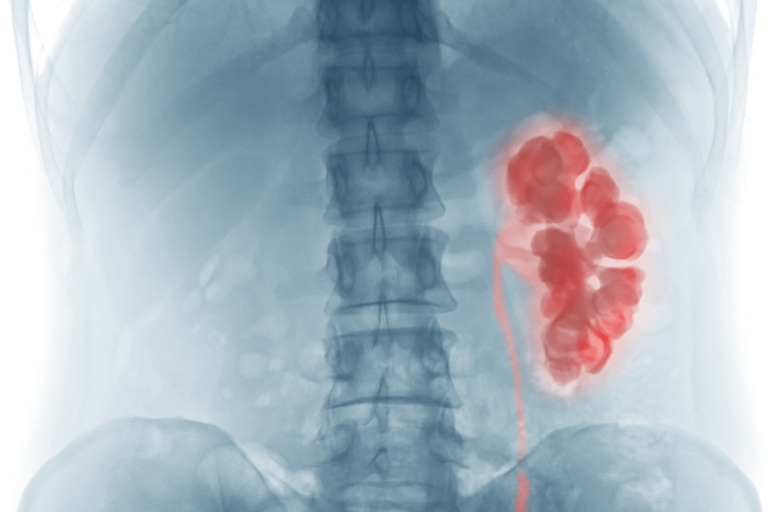

La palabra hidronefrosis procede del griego. Está formada por las raíces hydro, que significa ‘agua’, y nephros, que es ‘riñón’. Es una patología que consiste en la hinchazón de uno o ambos riñones. La razón es que no se consigue drenar la orina y esta se acumula.

La hidronefrosis, como acabamos de señalar, consiste en la inflamación de uno u ambos riñones porque son incapaces de vaciar la orina que producen. Tal y como explica un artículo de la Clínica Cleveland, esta entidad puede cursar de forma crónica o aguda.

La acumulación de líquido en los riñones puede hacer que se deteriore su función. Estos son órganos fundamentales para la depuración de toxinas del organismo. La insuficiencia renal puede ser una condición grave que ponga en riesgo la vida.